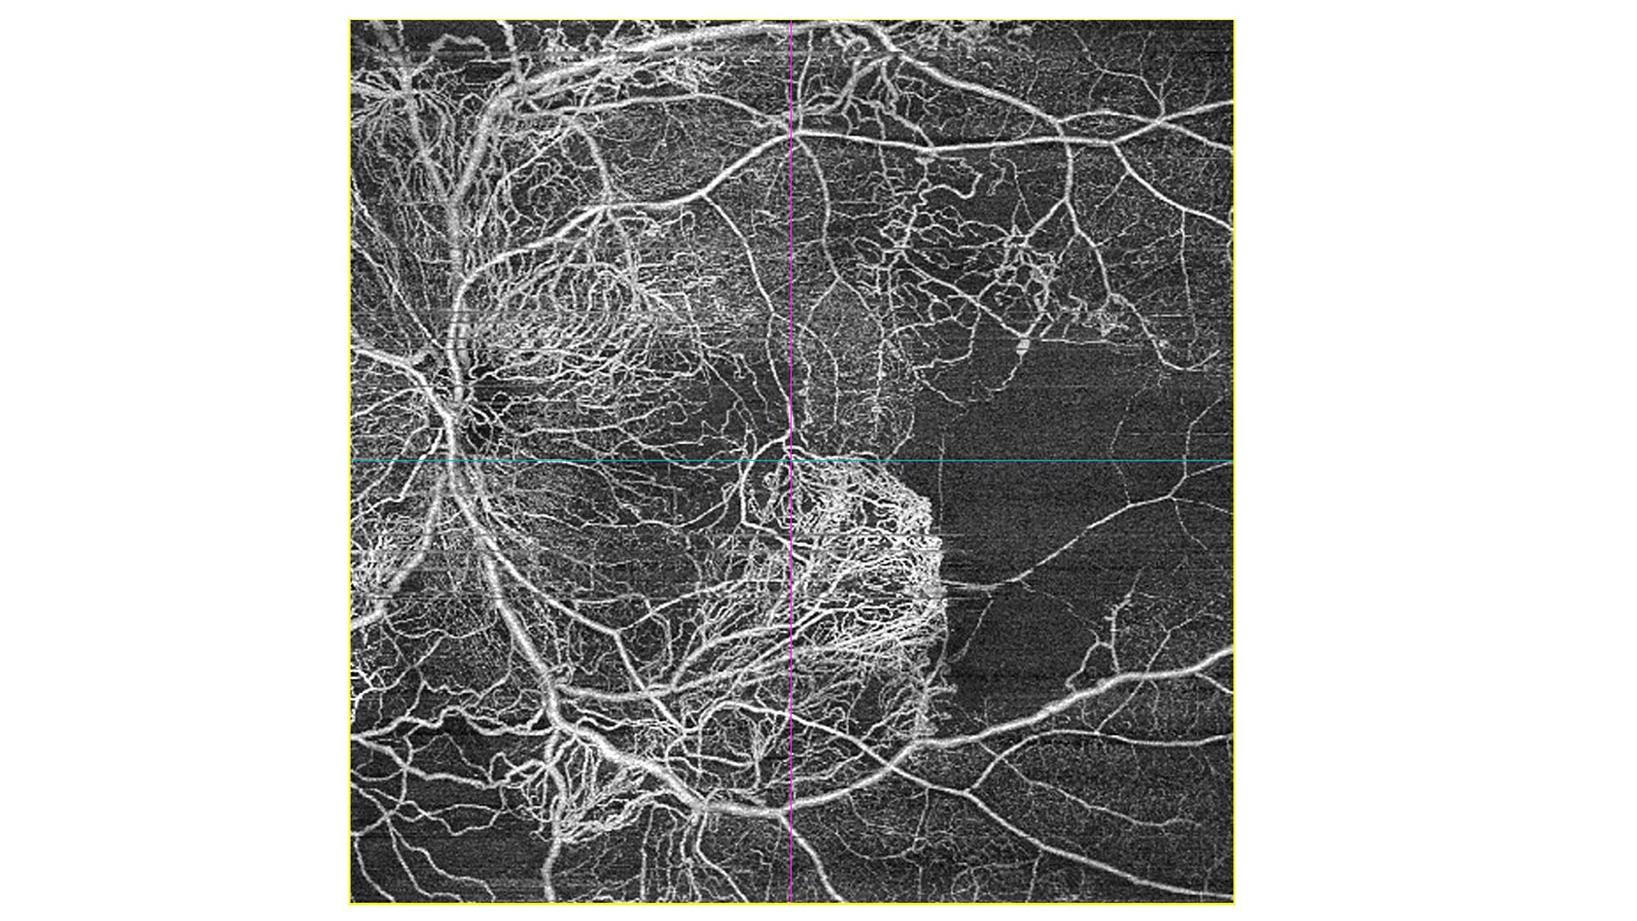

- NEW 510k CLEARANCE SUPPORTS MORE INFORMED DECISION MAKING & PATHOLOGY DETECTION: Showcasing optical coherence tomography angiography (OCT-A) with ZEISS CIRRUS AngioPlex® with noninvasive imaging of the retinal and choroidal vasculature; now with 510k clearance and CE approval, ICGA for CLARUS® 700 offers FA + ICG simultaneous capture.

ZEISS will also showcase its latest in OCT technology, providing enhanced details and insights to assist eyecare practitioners when examining patients and managing diseases. The implementation of best practices is helpful to maximize the clinical utility of OCT-A. In recognition of this, ZEISS has released OCT-A Simplified, a step-by-step eBook by Ricardo Luz Leitão Guerra, MD, MSc, FICO. The guidebook makes OCT-A more accessible to eyecare practitioners, covering image acquisition, analysis, and interpretation providing practical insights clinicians can apply immediately in clinical decision-making. Copies of the OCT-A Simplified ebook will be available at AAO at the ZEISS booth #2261.